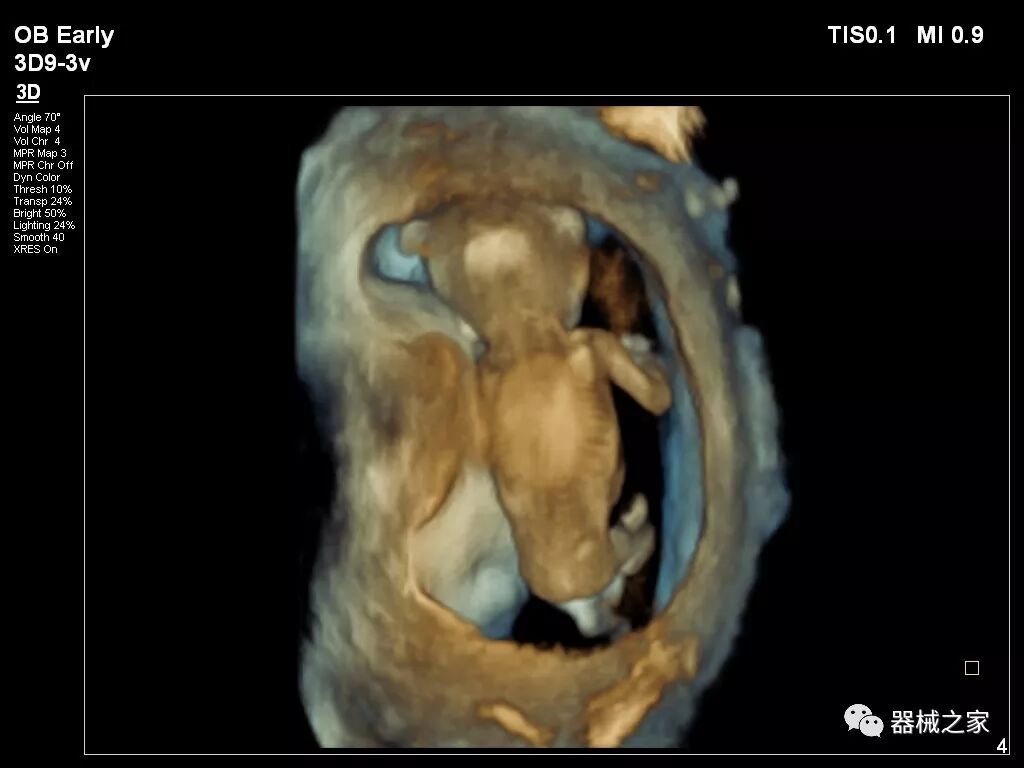

在RSNA 2018上发布的新成像被开发用于解决胎儿心脏和脑部成像问题。由于体积小且心率极快,因此难以进行详细的胎儿心脏评估。在18周时,胎儿的心脏大小与橄榄相当,每分钟跳动约150次。此外,结构本身非常复杂,婴儿不断运动,它始终是一个移动的目标。成像很重要,因为先天性心脏缺陷会影响全球每110个婴儿中的一个。

GE Healthcare用于胎儿超声的胎儿心脏和血管分析软件,在Voluson E10上提供,有助于在不到三分钟的时间内评估胎儿的心脏形状,大小和收缩性。称为辐射流的功能以三维视图显示血流。它还可以帮助显示缓慢流动的血液,例如神经血管循环。

Voluson E10

2018年发布的另一个例子是飞利浦的TrueVue,它提供照片般逼真的渲染,并能够在三维超声图像上改变光源的位置。它允许用户改变照明条件以提高对比度。可以移动光源以改变阴影并增加更多深度感知。还可以推动光源穿过组织以对解剖结构进行背光。